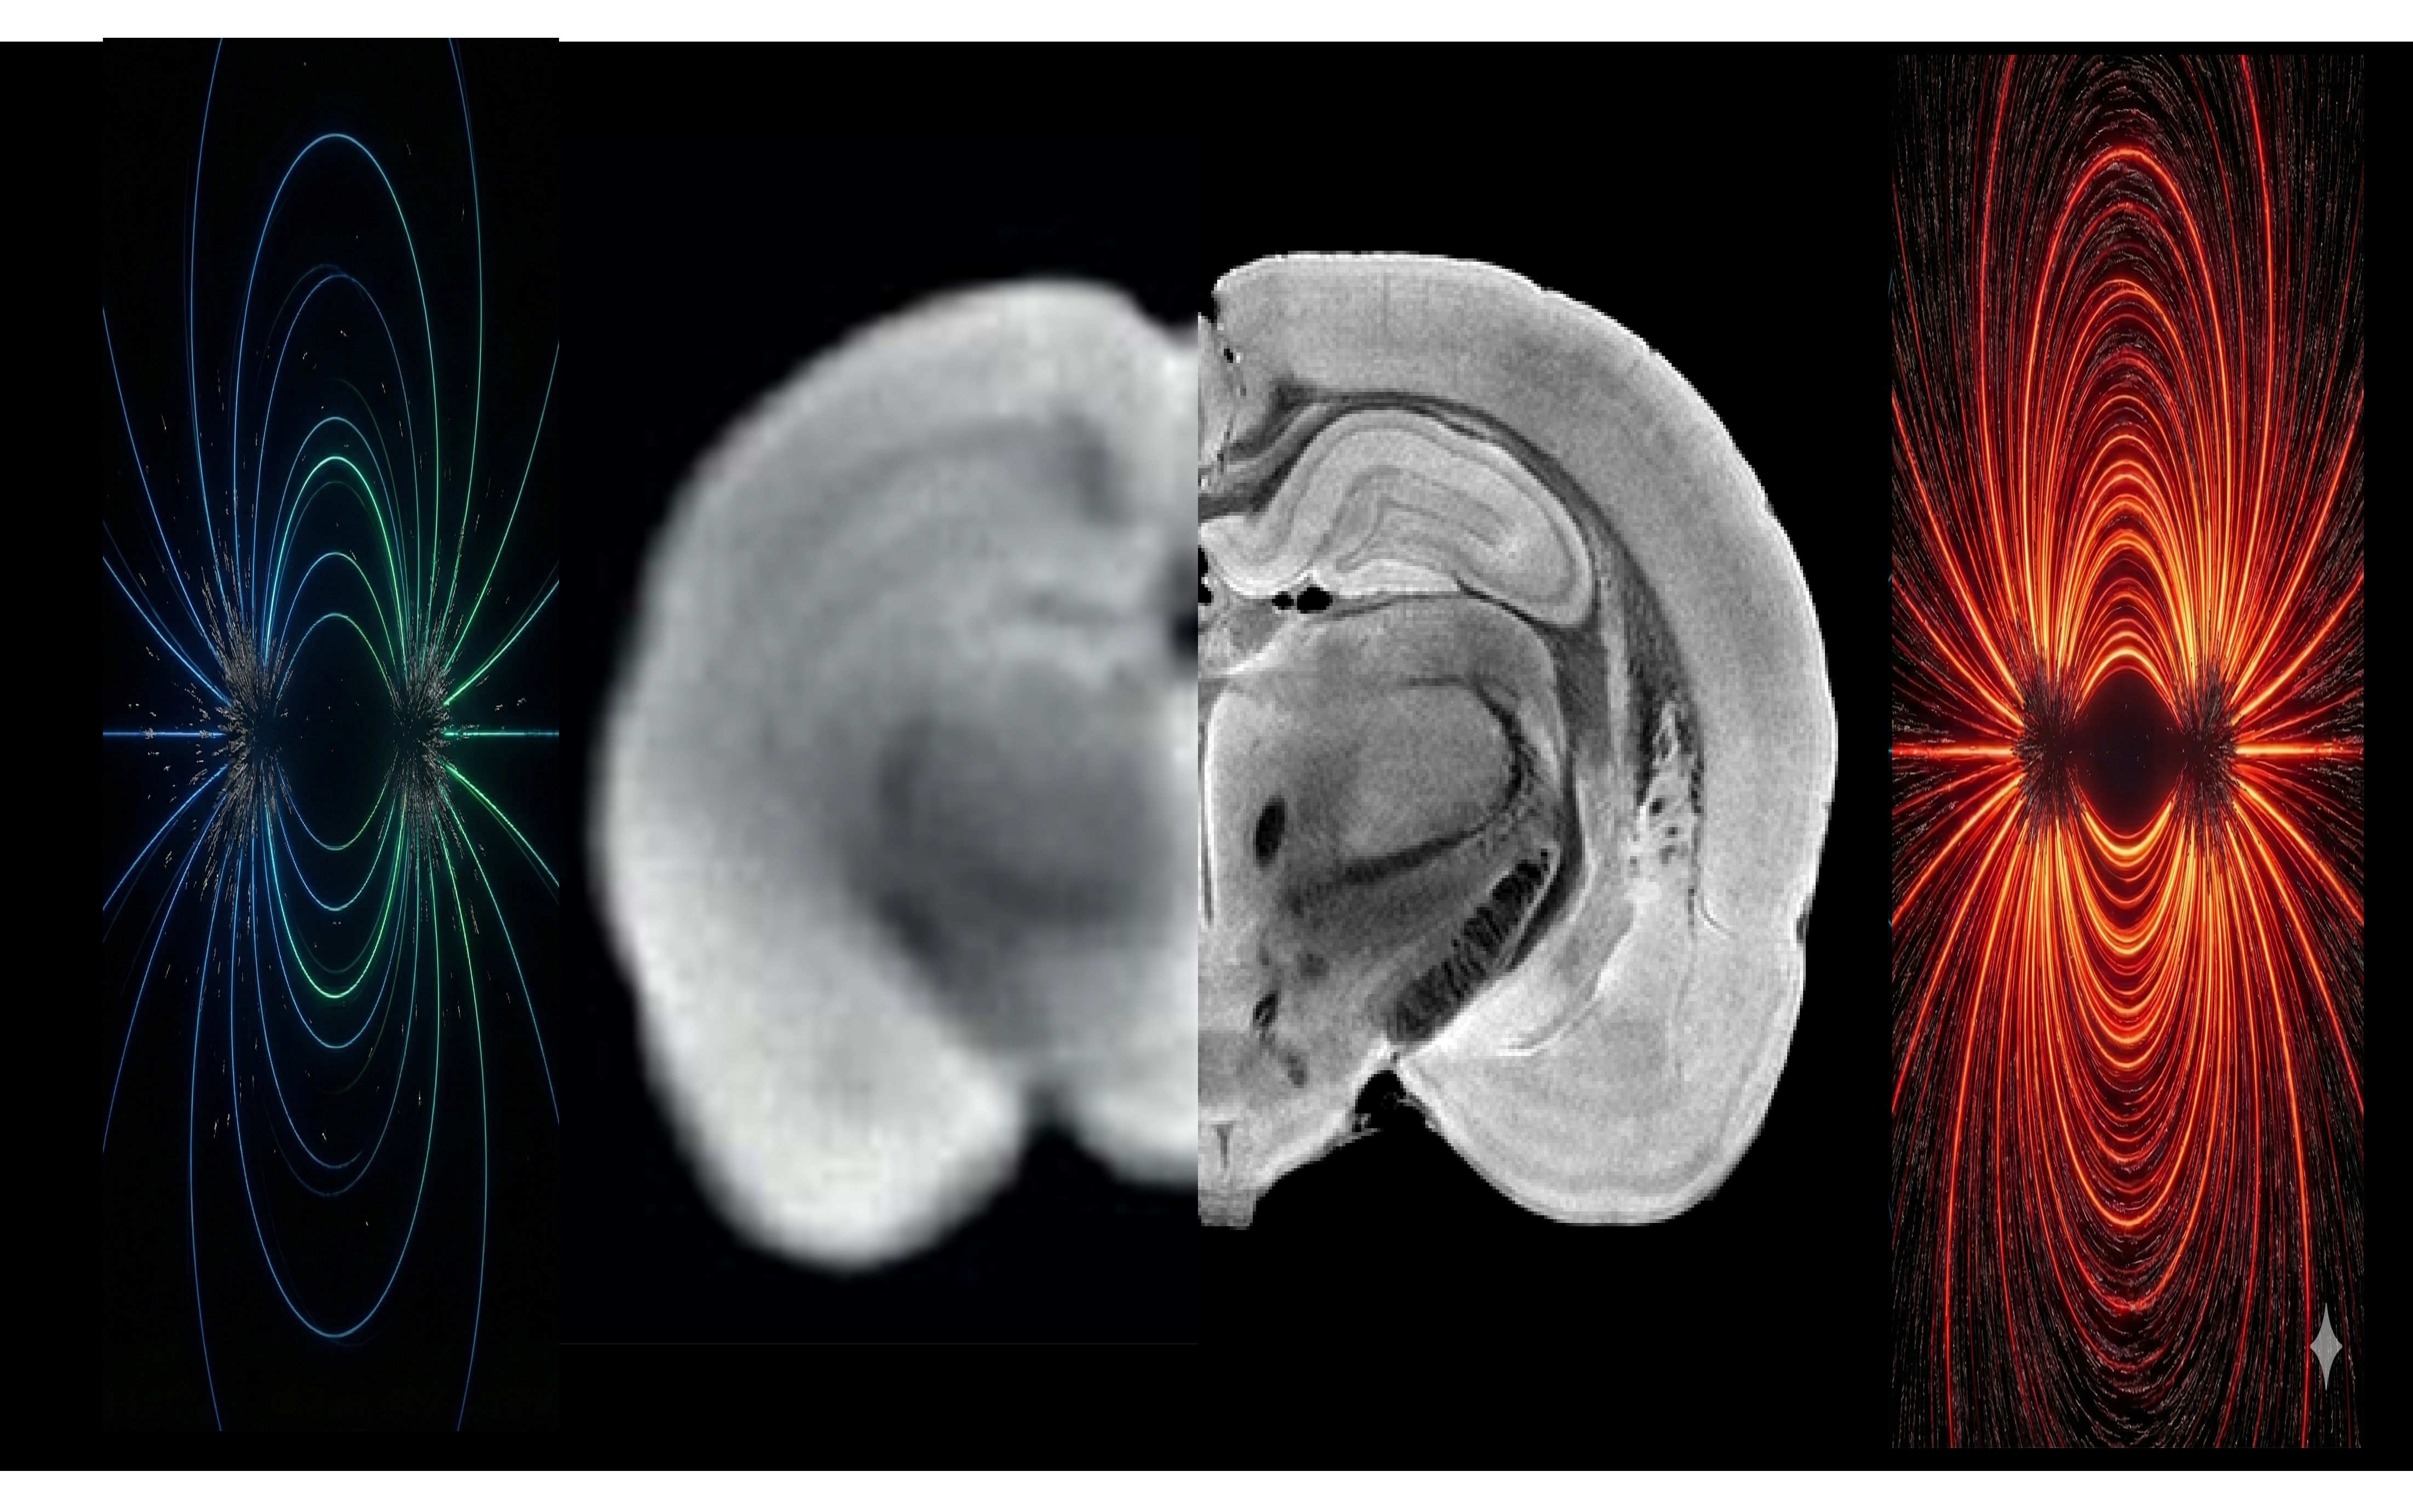

The brain is not only a network of electrochemical circuits, but also a living, active porous system that constantly remodels the “arena” in which neural activity unfolds. Our Lab investigates the mechanisms by which microscopic and mesoscale biophysical and biomechanical properties of the brain interact with neural activity, how they shape brain function, and how they change in health and in disease.

To do so, we develop advanced Magnetic Resonance Imaging methods in rodents in-vivo and in living brain slices in situ, to dynamically map and model such biophysical tissue properties. We push our ultrahigh field MRI systems to their very limits, using custom-built equipment, making them effectively in-vivo microscopes. We further harness simultaneous optical and electrical readouts to obtain multimodal vistas that enable discovery of the underlying biological drivers. We then use causal perturbations including optogenetics, focused ultrasound, and targeted chemical interventions, to manipulate both neural dynamics and the tissue’s mechanical state, allowing us to close mechanistic loops rather than rely on correlations alone.

Our research sits at the intersection of magnetic resonance, biophysics, chemistry, neuroscience, and signal processing. Projects in the lab are highly interdisciplinary and span scales and techniques: from magnetic resonance physics and pulse sequencing, through quantitative biophysical modelling, advanced image reconstruction, denoising, and computational analysis, to neural activity readouts (calcium imaging/recordings, electrophysiology) and behavioural experiments in animal models of plasticity and disease. Students typically work across methods, building new tools, applying them in experiments, and extracting biological insight from complex data.